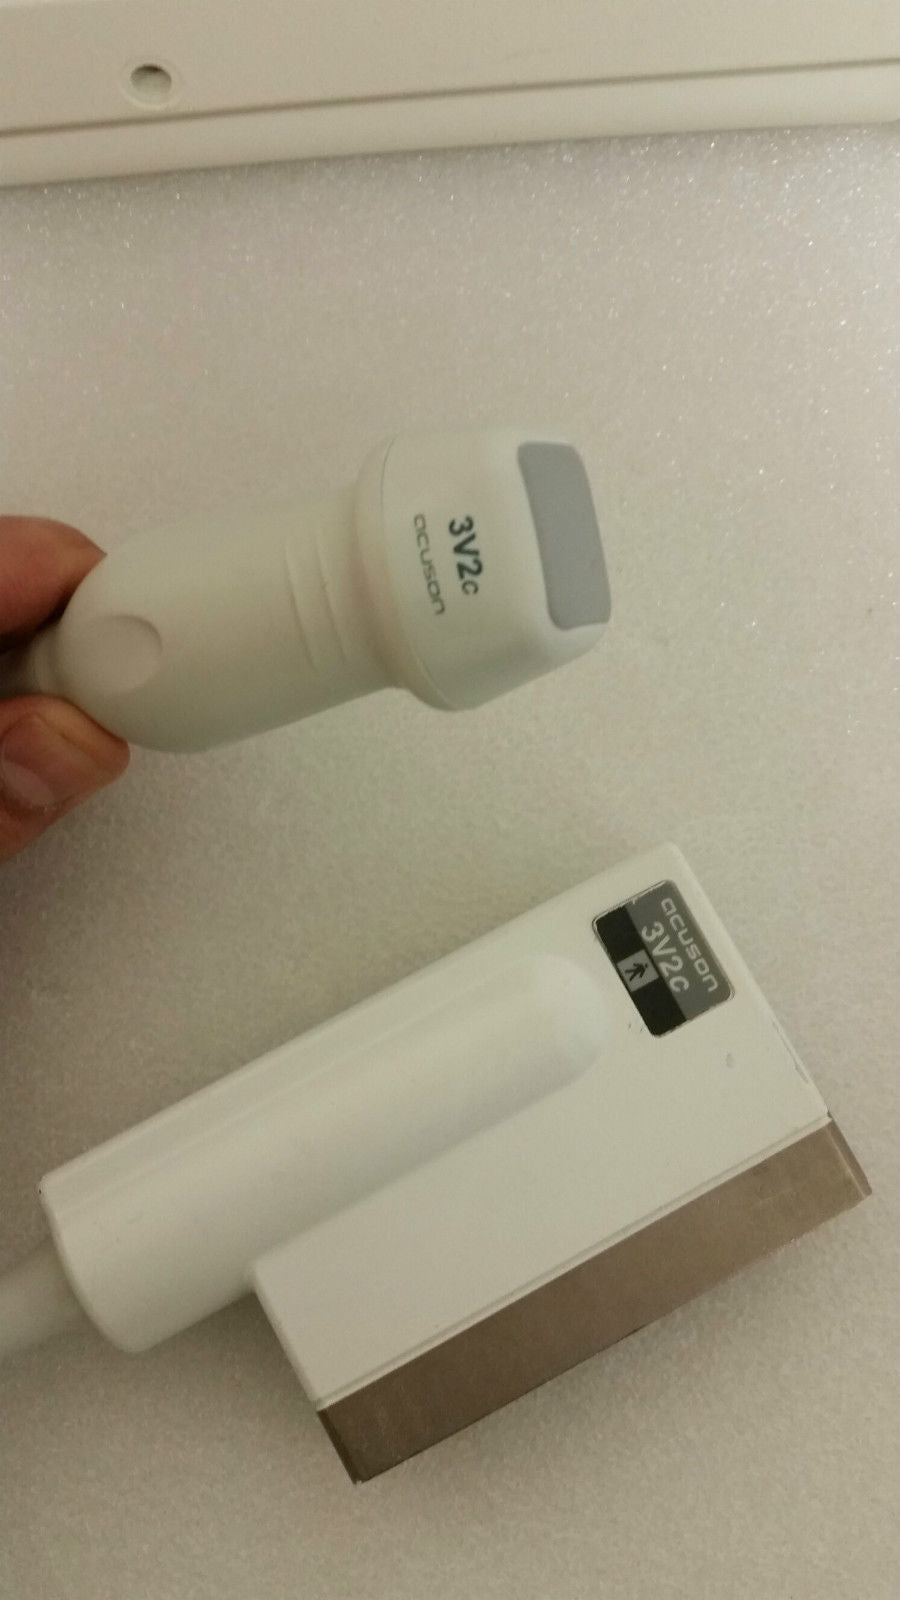

The Acuson Cypress Cardiac Vascular Ultrasound Machine is engineered for exceptional imaging and diagnostic accuracy. Its advanced technology allows for detailed visualization of cardiac and vascular structures, which is essential for healthcare providers. The inclusion of the 3V2c and 7L3 probes enhances its versatility, making it suitable for various clinical applications. As a result, this machine is a crucial tool in modern cardiology and vascular assessment.